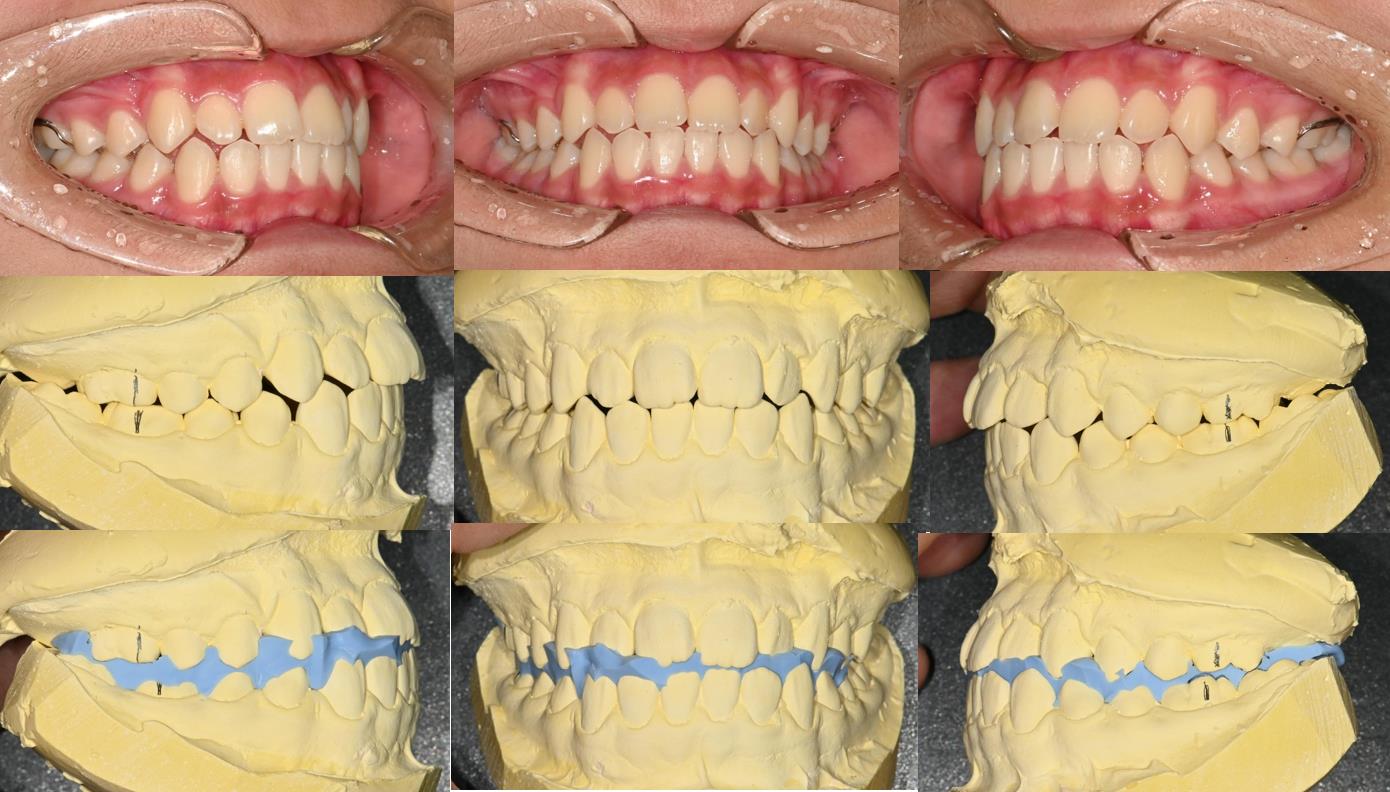

The reason why it becomes like this is the lower jaws rotate upwards with the temporal bone being unbalanced. Due to the temporal bone being unbalanced, the bone rotates to the left and makes the lower jaw rotate backward.

As we can tell by the image below, the more the lower jaw goes back, the head comes forward and becomes a straight neck.